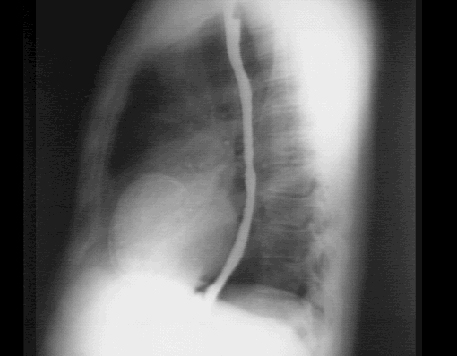

In this PA chest X ray with barium swallow it is demonstrated at the apex of the

left ventricle.